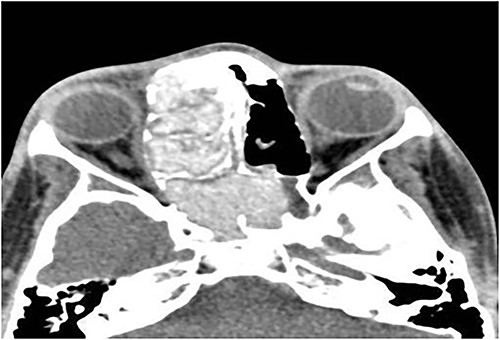

A 14-year-old male presented with a history of bilateral nasal obstruction for 3 years associated with snoring and postnasal discharge. Endoscopic examination showed bilateral nasal polyposis. CT scan of the paranasal sinuses (Fig. 3) & FESS, via which the sinuses were found full of polyps, mucin and fungal debris, confirmed the diagnosis of bilateral AFS. The patient continued on postoperative medical treatment and remained symptoms-free for 2 years follow-up.

Axial CT paranasal sinuses shows heterogeneous opacities filling the ethmoid and sphenoid sinuses bilaterally with hyperdense contents. The ethmoid sinus shows expansion with partial dehiscence of the right lamina papyracea.